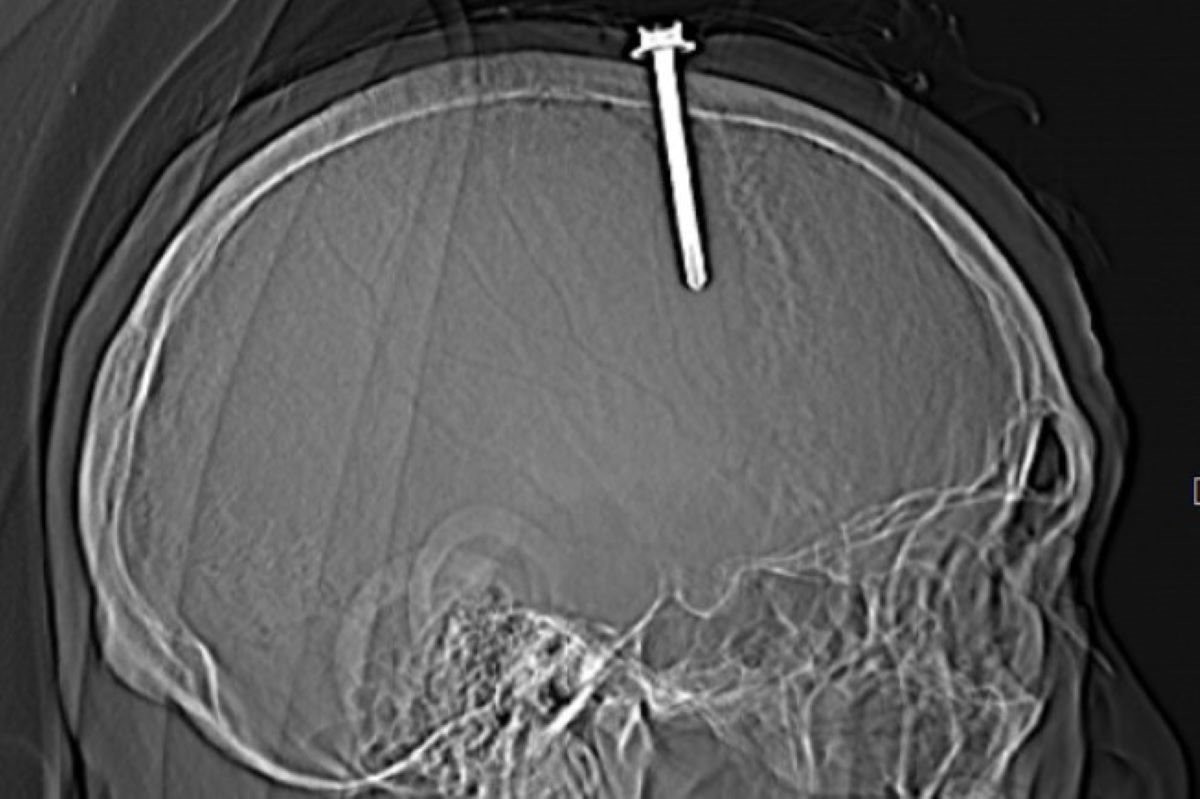

Ngày 16-7, tin từ Bệnh viện Đa khoa tỉnh Thanh Hóa cho biết các y, bác sĩ của bệnh viện vừa phẫu thuật cứu sống thành công một bệnh nhân bị một cây đinh dài 5 cm đâm xuyên hộp sọ do bệnh nhân tự đóng vào đầu.

Trước đó, Bệnh viện Đa khoa tỉnh Thanh Hóa tiếp nhận bệnh nhân là L.Q.T. (63 tuổi, nam, ngụ tỉnh Thanh Hóa) nhập viện trong tình trạng bị một cây đinh đâm xuyên hộp sọ, nguy hiểm tới tính mạng.

Theo người nhà bệnh nhân, ông T. mắc bệnh trầm cảm. Gần đây, bệnh nhân thường xuyên mất ngủ, cảm thấy đau đớn, bứt rứt trong người. Khó chịu do cơn đau hành hạ, bệnh nhân đã tự đóng một cây đinh vào ngay đỉnh đầu của mình nhưng được người nhà kịp thời phát hiện đưa tới bệnh viện cấp cứu.

Qua thăm khám lâm sàng và kết quả chụp cắt lớp vi tính sọ não cho thấy bệnh nhân có vết thương sọ não, vết thương xoang tĩnh mạch dọc trên do dị vật kim loại cắm vào vùng đỉnh bên trái, cạnh xoang tĩnh mạch dọc trên. Dị vật có đường kính 0,5 cm, chiều dài 5,1 cm.

Nhận định đây là một trường hợp tổn thương nặng do vết thương dính xoang tĩnh mạch dọc trên thông trực tiếp với hội lưu các xoang dọc trên, nên nguy cơ chảy máu ồ ạt và khó cầm, bệnh nhân có thể tử vong cao nếu không được phẫu thuật lấy dị vật kịp thời.

Ngay lập tức, các bác sĩ đã chuyển bệnh nhân về phòng mổ cấp cứu khẩn cấp. Sau hơn 2 giờ làm việc, các y, bác sĩ đã phẫu thuật thành công, lấy cây đinh dài hơn 5 cm ra khỏi đầu bệnh nhân.

Sau nhiều ngày theo dõi và điều trị, sức khỏe bệnh nhân hồi phục tốt và đã được cho ra viện về nhà tiếp tục thực hiện các phác đồ điều trị.